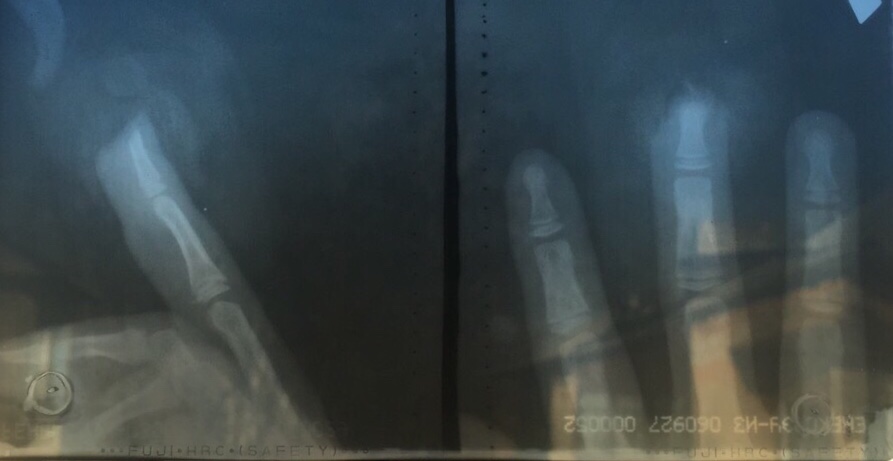

Это снимок руки моего сына. Я хз, как можно было так прищемить палец, но случилось то, что случилось.

По итогу: часть косточки удалена, т к была раздроблена и восстановлению не подлежит(2 мм, если верить врачу) , удалена ногтевпя пластина, но ложе не задето и ноготь обещают — отрастёт. Но... палец будет короче на половину ногтевой пластины😞